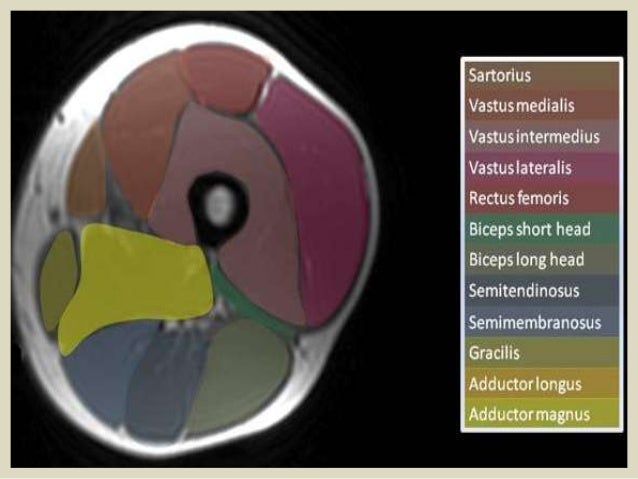

Upper Thigh Muscles Ct Anatomy - Lower Extremity Mri Anatomical Atlas / The pectoralis muscles are found on each side of your upper chest.. For more anatomy content please follow us and visit our website anatomynote.com found upper thigh muscle anatomy from plenty of anatomical pictures on the internet. The thigh is the area between the hip and the knee joint. Sartorius, rectus femoris, vastus medialis, vastus lateralis, vastus intermedius posterior thigh muscles: The adductor muscles form the fleshy mass on the medial side of the thigh. The upper limb muscles fall into three groups.

Upper thigh muscles ct anatomy : Want to learn more about it? Upper body muscle anatomy conclusions. Nine muscles cross the shoulder joint to move the upper arm. Dummies helps everyone be more knowledgeable and confident in applying what they know. Muscles of the posterior cervical and upper thoracic spine 1. Muscles adapted for loaded versus unloaded actions. The upper limb muscles fall into three groups. A complete list of muscular system quizzes; 2, vastus medialis & intermedius muscles. I'll be flicking between the two models. Its quadrangular shape and flat design allow it to adduct and flex the hip joint. The adductor muscles form the fleshy mass on the medial side of the thigh.

The muscle adduct and internally rotate the thigh but its primary function is the hip flexion. I'll be flicking between the two models. This is a table of skeletal muscles of the human anatomy. Pictures of upper thigh muscles. While the thigh muscles will be slip into the anterior, medial and posterior groups. Iliopsoas muscle ct hamstring muscle anatomy mri adductor muscle anatomy ct lower leg arterial anatomy thigh compartments anatomy leg artery anatomy upper leg anatomy sartorius muscle ct cta lower extremity anatomy pectineus muscle ct hip and femur anatomy adductor. Lesser trochanter to linea aspera nerve supply:( double nerve. Muscles in the posterior compartment of the thigh. Nine muscles cross the shoulder joint to move the upper arm. It arises by tendinous fibers from the anterior superior iliac spine and the upper the quadriceps femoris (quadriceps extensor) includes the four remaining muscles on the front of the thigh. ·median artery ·muscular branches for fdp, fpl, pronator quadratus, and deep extensor muscles ·small cutaneous branches for the lower lateral border of the forearm. As the name implies they adduct the thigh at the hip joint. Each type of muscle tissue in the human body has a unique structure and a specific role.